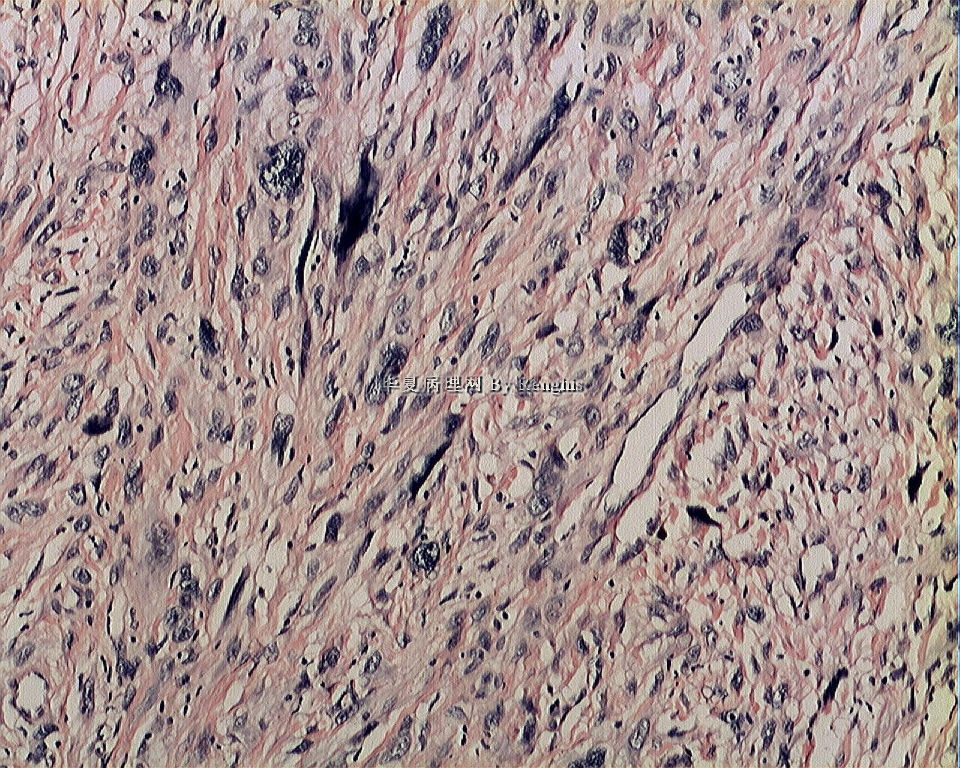

女,29岁,左大腿内侧肿物直径2.8cm,切面灰白、实性、质中,似有包膜。

本例就形态学而言不太符合纤维肉瘤,对于一个多形性和异型明显的肿瘤首先不考虑纤维肉瘤的诊断加上车辐状结构首先还是考虑纤维组织细胞肿瘤。

本人认同此例是一例比较典型的纤维肉瘤,瘤细胞程束状、鱼骨状及编织状排列,部分瘤细胞异型性明显,免疫组化vimentin阳性,SMA灶状弱阳性,desmin阴性,S100阴性,CK阴性,EMA阴性,余记不得了,明天看看再上传。